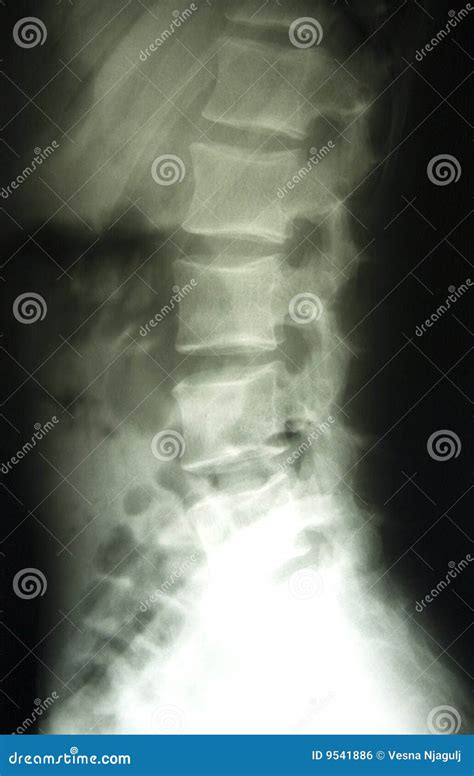

A Lower Back X Ray is a common, non-invasive imaging test that uses a small amount of radiation to create pictures of the lumbar spine. The lumbar spine consists of the five vertebrae in your lower back. By capturing these images, doctors can evaluate the bones, joints, and overall alignment of the lower spine.

Unlike more advanced imaging studies, such as an MRI or CT scan, a plain X-ray focuses primarily on dense structures like bone. While it cannot show soft tissues like nerves, discs, or muscles in great detail, it is highly effective for identifying bone-related problems that often cause chronic pain.

Undergoing a Lower Back X Ray is a straightforward and generally quick process. You will be asked to change into a hospital gown to ensure no metal objects, like zippers or jewelry, interfere with the image quality. You may be required to stand, sit, or lie down in different positions—such as on your side or back—so the technician can capture images from multiple angles. This ensures a comprehensive view of the lumbar region.

What Can Be Seen on a Lower Back X Ray?